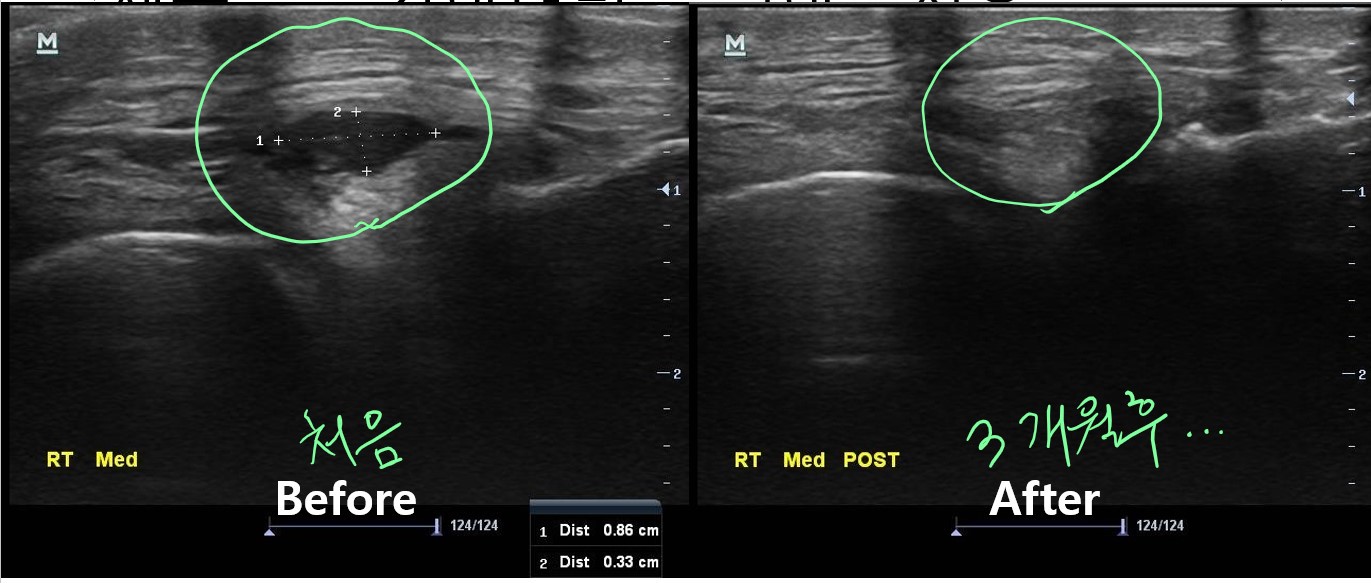

당산 정형외과, 당산역 정형외과, 영등포 정형외과안녕하세요 오늘은 충격파 치료만으로 해결이 되지 않던 석회성 건염 환지의 치료 사례를 보여드리겠습니다. 얼마전 진료실에 연세가 70이 넘으신 어르신이 오셨습니다.나 : 어르신 어디가 아파서 오셨어요? 환자 : 어깨가 아파요 나 : 아픈지 얼마나 되셨어요? 환자 : 6개월 정도는 된거 같네요. 나 : 그동안 치료 안받으셨어요? 환자 : 치료했죠. 다른 병원에서 어깨에 석회가 끼었다고 해서 그동안 계속 치료 받았는데도 계속 아프네요 나 : 아 그래요? 무슨 치료를 받으셨어요? 환자 : 석회를 깨트리는 충격파 치료라고 해서 받았어요. 거의 10번은 받은거 같은데...석회성 건염(석회화 건염)을 진단받고 체외 충격파 치료만 무려 10회 이상 받았다는 환자, 팔을 ..